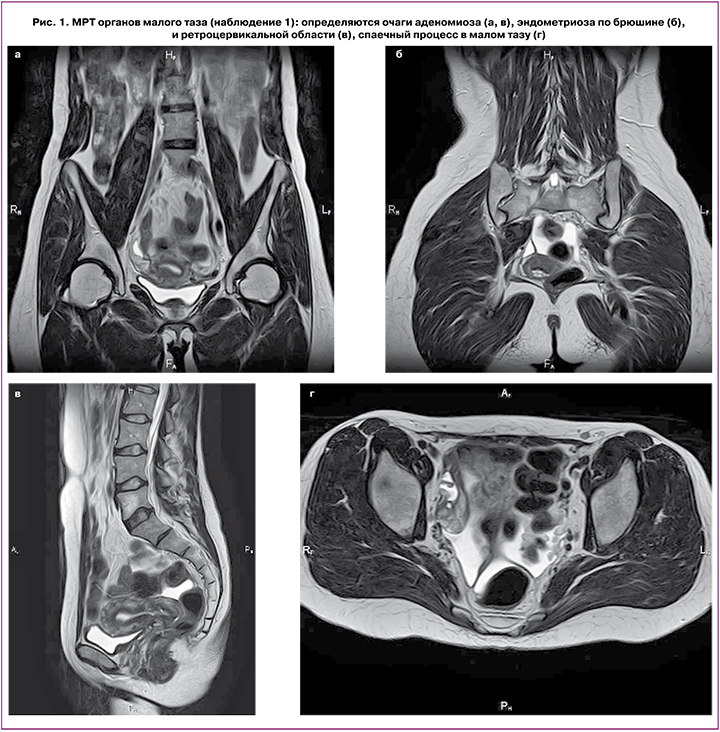

В возрасте 47 лет (июль 2020 г.) на 2-й день менструации у пациентки остро возникли: затруднение дыхания, боли в грудной клетке и спине, одышка. По месту жительства на обзорной рентгенографии органов дыхания диагностирован правосторонний пневмоторакс (снимки не представлены). Пациентка госпитализирована, произведено дренирование плевральной полости. После купирования симптомов выписана домой в удовлетворительном состоянии. Однако через месяц, за сутки до начала менструации пневмоторакс повторился. После обследования в сентябре 2020 г. в Ставропольском краевом диагностическом центре пациентке произведена видеоторакоскопия справа, резекция сухожильного центра диафрагмы, костальная плеврэктомия. При гистологическом исследовании биоптатов диагностирован эндометриоз купола диафрагмы. После операции назначена терапия аГнРГ (бусерелин-депо 3,75 мг 1 раз в 28 дней) на 6 месяцев. В связи с ограничением длительности приема аГнРГ в 2021 г. пациентка обратилась в ФГБУ «НМИЦ АГиП им. В.И. Кулакова» для решения вопроса о дальнейшей тактике ведения. При проведении МРТ малого таза выявлено: диффузная форма аденомиоза I ст., спаечный процесс в малом тазу, очаги эндометриоза по серозному покрову матки и яичников, в клетчатке таза, по правой круглой связке матки, по брюшине таза, в ретроцервикальной области, очаги по крестцово-маточным связкам (рис. 1 а–г).